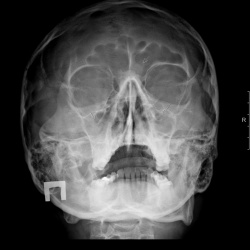

Анамнеза к сожалению не знаю. В направлении: о. гайморит?

Есть ли затенения в медиобазальном отделе слева, затенены в/ч пазухи или неправильная установка?